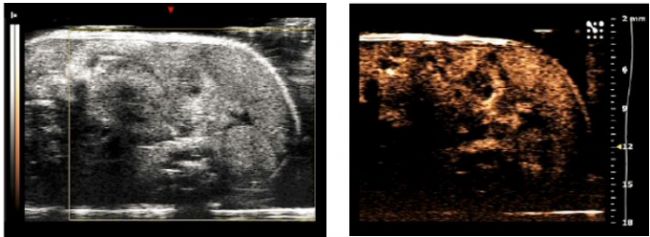

Deliver 产品主要是在Prime上负载临床上化疗用药doxorubicin(DOX)的载药微气泡,使微气泡除了可作为超声造影剂以外,同时可达到超声波驱动的药物释放和治疗肿瘤的目的。Deliver最大优势在于注入活体内后,能先利用微气泡的显影功能在超声波影像上呈现肿瘤的位置,接着通过在目标位置加强超声波可驱动Deliver内药物在靶向部位大量释放,达到肿瘤局部化疗的功效。图10显示骨肉瘤上利用Deliver的治疗结果:,在治疗后第五天可以利用超声波显影剂观察到肿瘤出现坏死(necrosis)。

图10左图为Deliver的荧光显微镜图像;右图为利用超声波驱动Deliver释放DOX进行治疗,可以观察到在治疗后第五天肿瘤内部出现坏死

Figure 10 Left:Fluorescence microscopy image of deliver; Right: Tumor necrosis on day 5 after injection of Deliver.